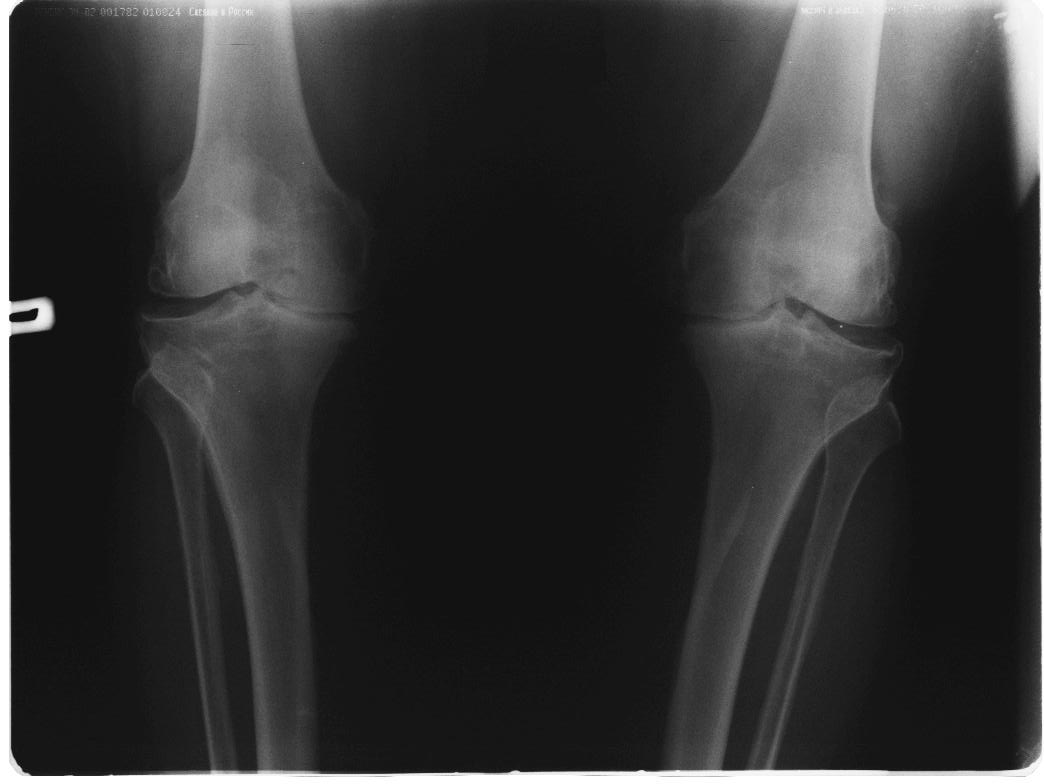

вообще, то в комплекс симптопатической терапии входят всякие медикаменты + ИСЖ (гиалуронаты) + гормоны при "мокром" суставе + физиолечение + грязи + солнце - воздух и вода + доброе слово и участие доктора и все это.... не удел ортопеда -хирурга. Это ближе к терапии. Чуть агрессивнее различные артроскопические санации и манипуляции - временно помогает + ИСЖ + фиксаторы + ортезы + аппараты + трость и костыли + коляска. Однако судя по рентгенограммам - суставы приговорены к эндопротезированию.

Глядя на снимки, кроме оперативного лечения в голову ничего не приходит. Хотя бы корригирующая кортикотомия б/б кости с минимальной внешней фиксацией. Высылаю пример.

Откровенно говоря, прочитав ваше суждение по теме о возможности неоперативного лечения двустороннего гонартроза, варусной деформации,сильно

Каждому методу свое время и место. у обсуждаемого пациента очевидна перегрузка медиальных отделов суставов с разрушенными суставными поверхностями, каким образом, вы представляете себе облегчить боли НПВП (разнообразие которых столь велико, что больному не хватит жизни и здоровья, чтобы все перепробовать, но идля *участливого* доктора всегда есть путь к отступлению - не помогает один, давайте попробуем другой - бесконечный,

Я всячески поддерживаю тактику оперативного вмешательства. Но просто тема консервативного лечения, надеюсь Вы согласитесь, на форуме обсуждается КРАЙНЕ РЕДКО И НЕОХОТНО. А применительно к выложенным R-граммам, конечно, показано Эндопротезирование, но только заголовок обращения сразу расставляет приоритеты в пользу консервативных методик. Причины тому могут быть самые разнообразные, нам о них не сообщили. Так зачем же предлагать коллегам то, чего они делать не будут?